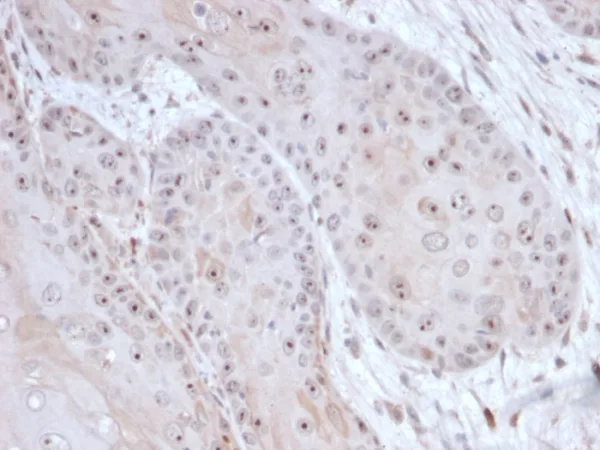

Formalin-fixed, paraffin-embedded human tumor of unknown origin stained with DAXX Mouse Monoclonal Antibody (PCRP-DAXX-6E11) at 2ug/ml. HIER: Tris/EDTA, pH9.0, 45min. 2°C: HRP-polymer, 30min. DAB, 5min.